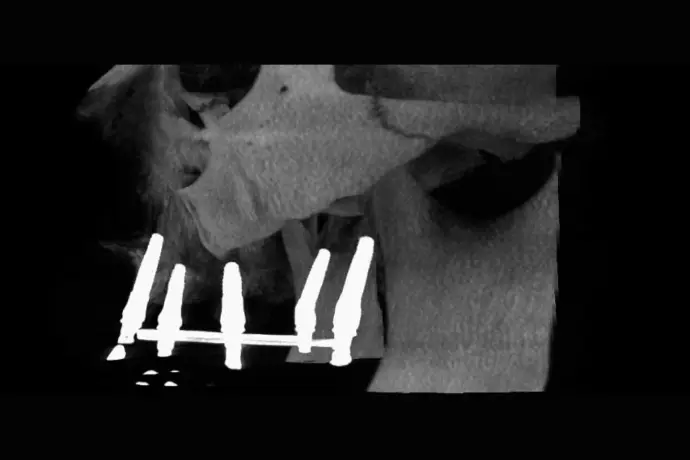

Référentiel Full Arch Club : All-on-4, All-on-X, palatal approach, trans-sinus, pterygoïdes, subpériostés personnalisés (sans zygoma de routine). Moins invasif, plus sûr.

• Master all concepts of FULL ARCH.

• Surgery and immediate loading witha bone graft-freeand predictable approach.